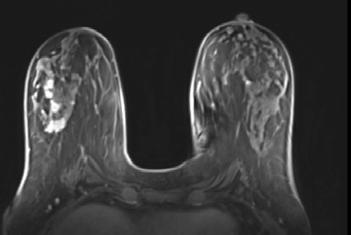

‘Voor een goede diagnose moet je samen met de radioloog alle infor matie in overweging nemen’, zegt prof. dr. Wiebren Tjalma, medisch coördinator van de borstkliniek. Hij geeft het voorbeeld van een vrouw van 55 die zelf een knobbeltje in haar borst ontdekte. Tjalma: ‘Tij dens het klinisch onderzoek voelde ik bij haar een letsel. Maar de beel den van de mammografie kwamen daar niet helemaal mee overeen: het letsel dat ik gevoeld had, leek me groter.’ Tjalma overlegde daarover met de radioloog: ‘Het was weefsel met erg veel klieren, waardoor we

De bijkomende beelden veranderden de hele aanpak.

eigenlijk niet goed konden zien of er eventueel nog een tweede letsel kon zijn. Daarom beslisten we om een bijkomende MRI en een echo te laten maken. Daarop zagen we inderdaad een tweede en een derde letsel in de borst.’

Na een biopsie in alle letsels bleek het om drie kwaadaardige gezwellen te gaan. Tjalma: ‘Dat ver anderde de hele aanpak. Eén gezwel konden we verwijderen met een borstsparende operatie, twee niet. Na overleg met artsen uit verschil lende disciplines was het advies om beide letsels te verwijderen, wat in de praktijk neerkwam op een borstverwijdering. Voor de patiënt was dat uiteraard een zware dobber, maar ook een geruststelling, omdat het tweede gezwel was ontdekt en behandeld. De multidiscipli naire aanpak voor de start van de behandeling was dus een groot voordeel voor de patiënte.’